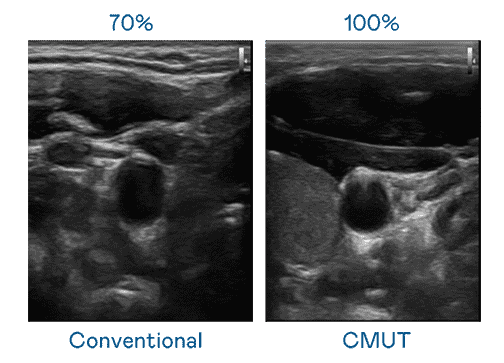

CMUT 技术是一种用电容式微机电元件来产生超音波讯号的技术。。。与传统 PZT 压电式技术相比,,,,CMUT 频宽增加 30%,,更宽频的超音波讯号让影像解析度大幅提升,,,是实现高影像品质医疗超音波扫描、、、、促进精准医疗发展的关键技术。。

大频宽带来超清晰影像

超音波影像的解析度高低,,首先取决于探头能发出的讯号频宽。。。。牛牛游戏 CMUT 可提供高清晰的超音波讯号,,提供高频宽、、、、高灵敏度、、影像纹理细节更高的超音波影像,,,协助医护人员缩短影像判读时间及利用精准的医疗影像进行诊断。。。